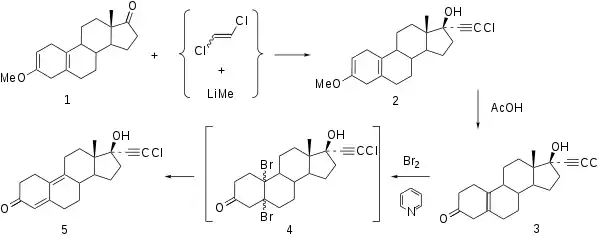

Synthesis